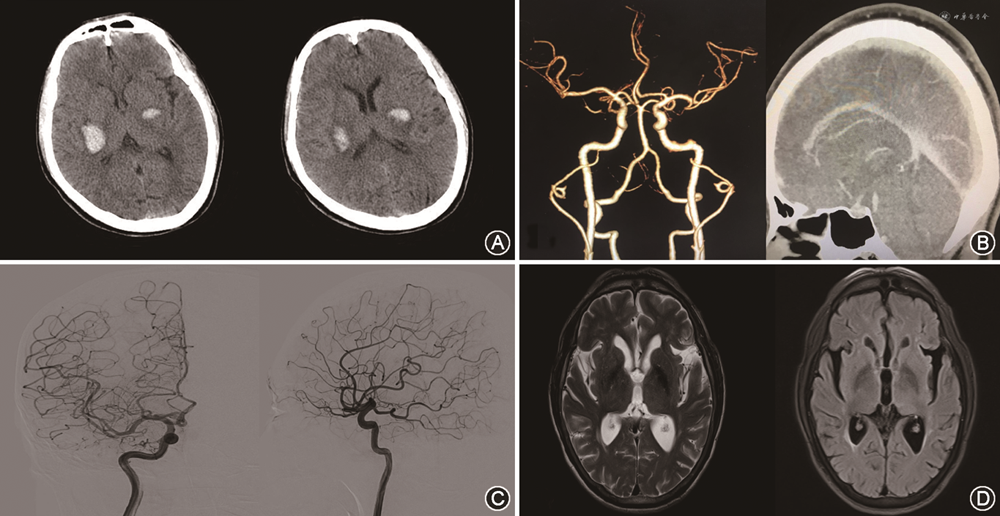

临床资料 患者男性,51岁,因“突发四肢乏力2 h”于2022年3月5日急诊入院。发病当时在进午餐,表现为突发双上肢持物不稳,伴行走醉酒样状态。既往有“高血压病”史10年,平素未规律服药控制;无其他脑血管疾病及口服药物抗凝史。入院时血压158/98 mmHg(1 mmHg=0.133 kPa)。嗜睡,双侧瞳孔直径2.5 mm,对光反射灵敏,双侧眼球活动正常,无视力障碍、视野缺损,双侧鼻唇沟对称,伸舌剧中,左上肢指鼻试验浅稳,右下肢跟-膝-胫实验弱阳性,左上肢肌力Ⅳ+级,右上肢及双下肢肌力Ⅳ级,双侧额面部及肢体浅、深感觉对称,双侧Babinski征阳性,颈抵抗阴性。急诊行头颅CT示:双侧基底节区高密度影,粗测左侧血肿体积约5 ml,右侧血肿体积约15 ml;CT动脉造影及CT静脉造影未见明显颅内动脉瘤、血管畸形以及静脉窦狭窄、闭塞等。凝血功能检查示:凝血酶原时间13.7 s、部分凝血活酶时间41.1 s、国际标准化比值1.03、D-二聚体1.26 μg/ml,均在正常范围内。入院后予止血、脱水、降压等保守治疗措施,次日意识状况好转为清醒,动态复查头颅CT示血肿稳定并逐渐吸收。入院1周患者病情稳定后行数字减影血管造影检查,未见明显颅内血管性病灶。左下肢肌力好转为Ⅳ+级,其余肌力好转至Ⅴ级。出院后行高压氧舱治疗2个疗程,随访1年时行头颅磁共振平扫、增强及血管成像检查示双侧基底节区软化灶,未见明显动静脉畸形、动脉瘤、海绵状血管瘤、动静脉瘘、烟雾病及脑肿瘤等征象,病情无复发,四肢肌力Ⅴ级(图1)。